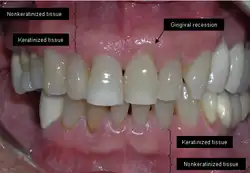

The soft tissue in the oral cavity is classified as either keratinized or nonkeratinized based on the presence of keratin in the epithelium.[3] In health, the soft tissue immediately around the teeth is keratinized and is referred to as keratinized tissue or gingiva. Alveolar mucosa is non keratinized oral epithelium and is located apical to the keratinized tissue, delineated by the mucogingival junction (MGJ). It should also be pointed out that mucosa can surround a tooth in health.[4] Nonkeratinized tissue also lines the cheeks (buccal mucosa), underside of the tongue and floor of the mouth. The lips contain both non-keratinized tissue (on the inside) and keratinized tissue on the outside, demarcated by the vermillion border. The dorsum of the tongue is keratinized and features many papillae, some of which contain taste buds.[5]

Exposure of the tooth root due to loss of keratinized tissue around the neck of a tooth is referred to as gingival recession. This can result in sensitivity or pain from the exposed tooth root surface (dentin is more permeable and soft compared to enamel and dentin is what makes up the tooth root).[6] Recession may also cause an unasthetic appearance especially if located in the anterior dentition (front teeth). While not all cases of gingival recession require surgical correction, there are various options if that is what the patient desires.[7] It should be reinforced that recession left untreated will not result in tooth loss, contrary to popular belief. Also, recession that is left untreated can be maintained and the inflammation kept at bay with proper brushing and oral hygiene technique.[4] On the other hand, if one desires to pursue corrective therapy, there are a wide variety of techniques ranging from autograft (one's own tissue, usually taken from the palate), allograft (another's tissue, cadaver tissue), xenograft (animal tissue, usually porcine or bovine) or simply repositioning of the tissue native to the site.[8]